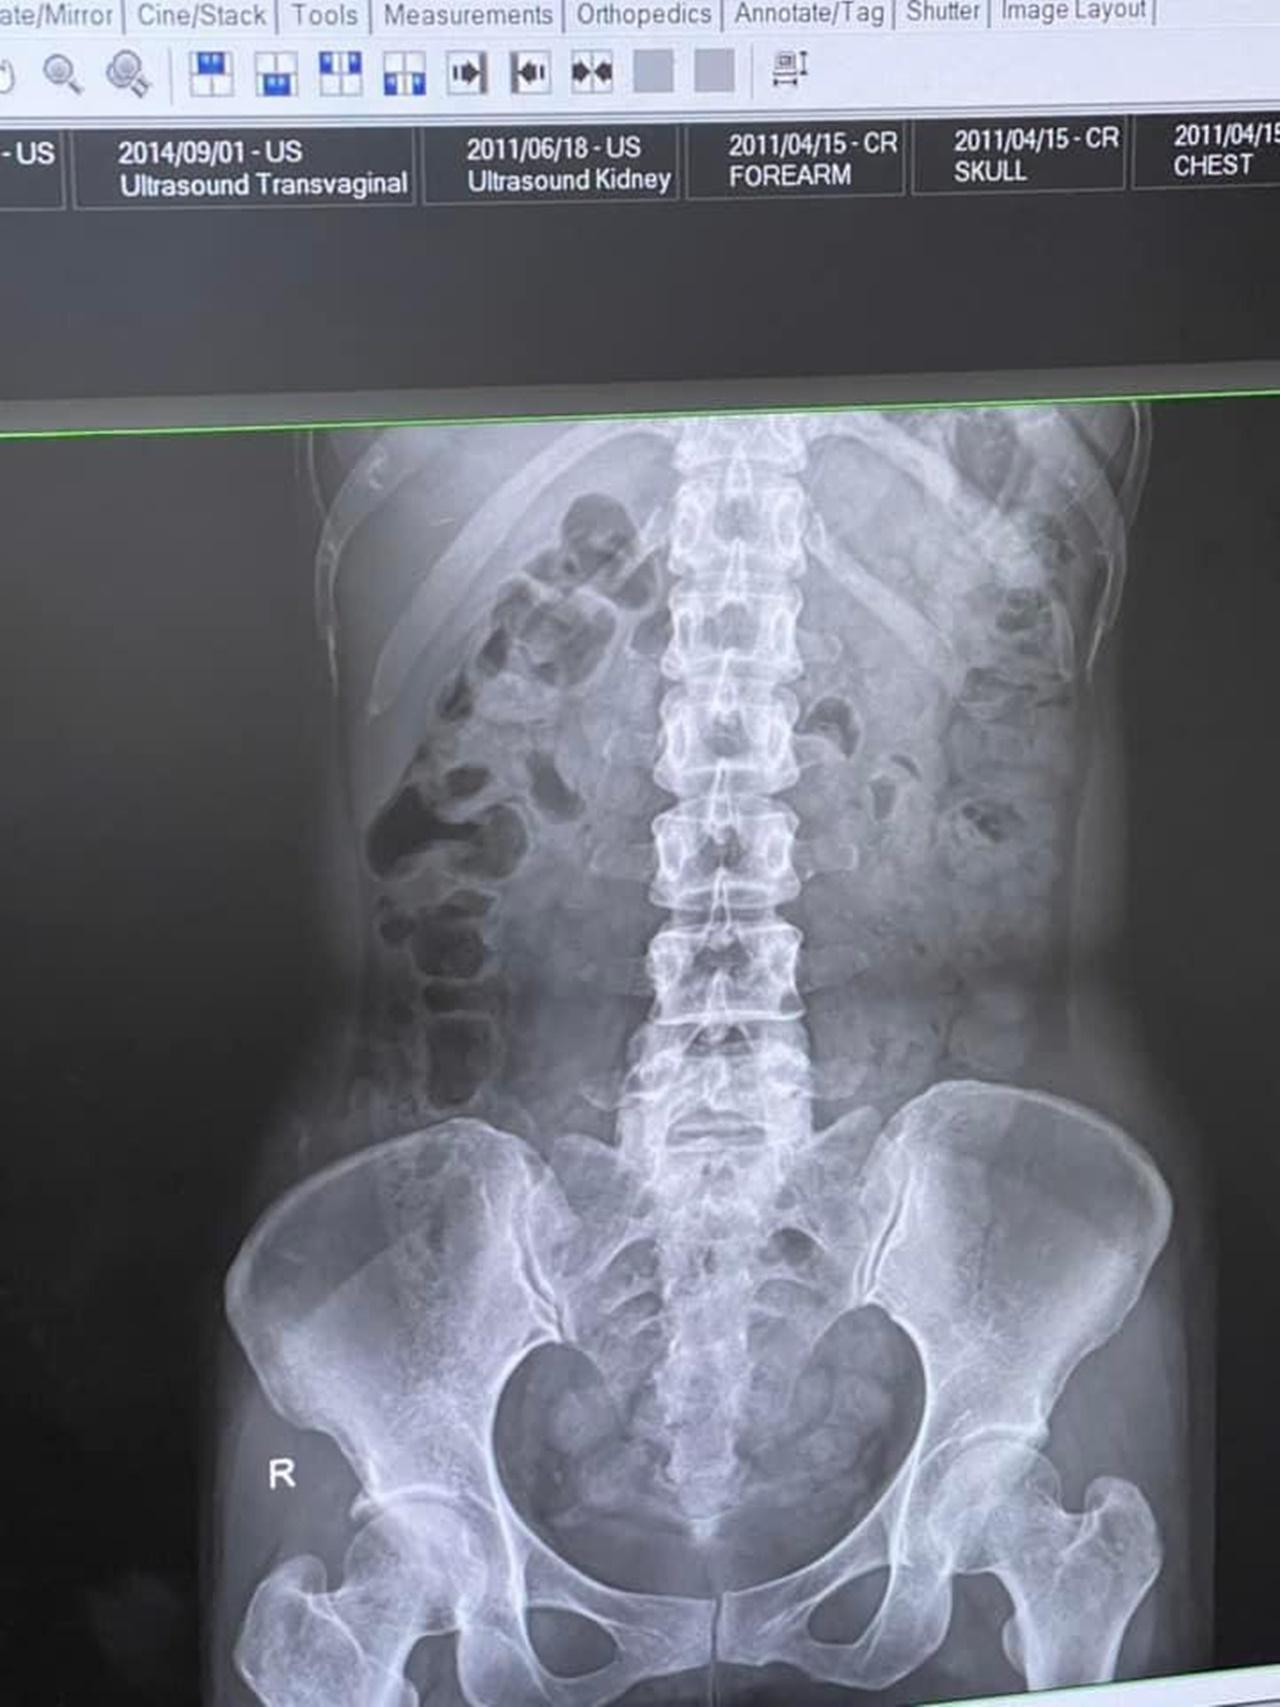

ในฟิล์มที่เห็นขาวๆ ก็คือ ขี้น้อนทั้งนั้นเลยค่ะ ลอยละล่องเป็นยองใย เยอะแค่ไหนถามใจเธอดู"